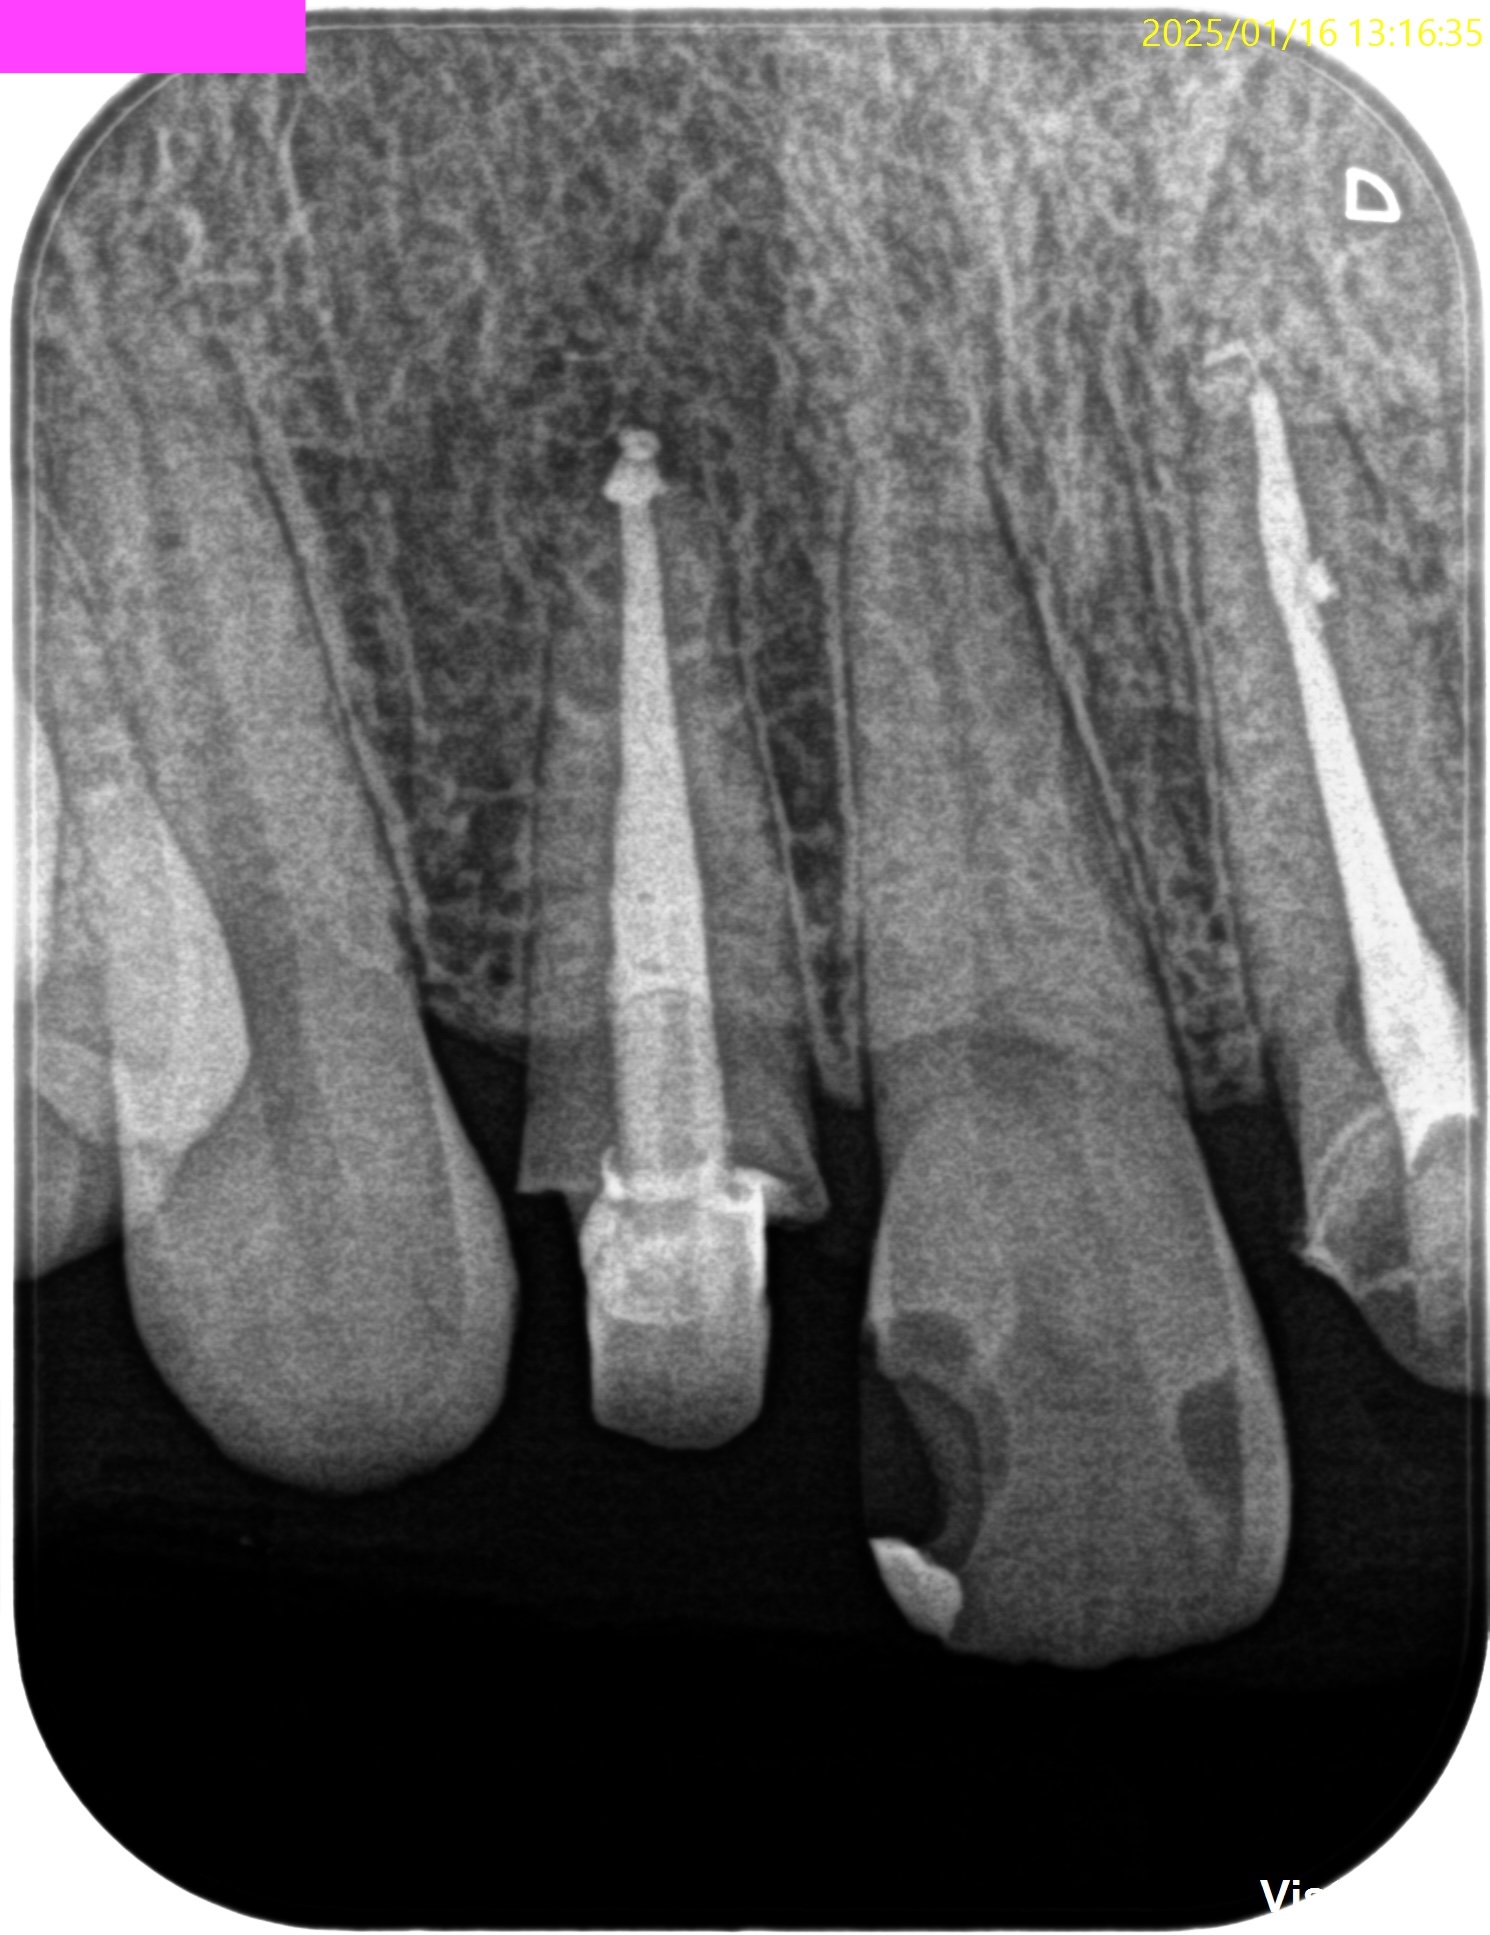

さておき、根充+支台築造後にPA, CBCTを撮影した。

#7

#10